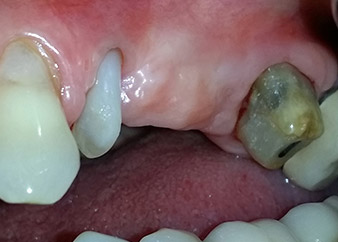

Einen Monat nach dem Eingriff waren sowohl die Schmerzen als auch die Entzündung an Zahn 24 minimal, die Zahnbeweglichkeit lag jedoch noch bei Miller-Klasse 2. Nach Freilegung und Reinigen des infizierten periapikalen und periradikulären Gewebes wurde das Ausmaß des Knochendefizits deutlich (Abb. 2 und 3).

An der bukkalen Wurzel fehlte der gesamte vestibuläre und distale Knochen. Das Attachment beschränkte sich weitgehend auf die palatinale Wurzel, was die anfängliche schlechte Prognose unterstreicht. Auch Zahn 27 wies ein verringertes horizontales Attachment (vgl. Abb. 12) und eine kleine apikale Aufhellung (Abb. 1) auf, allerdings ohne klinische Symptome.

Zunächst wurde in einem Versuch, das Paro-Endo-Problem zu lösen, an der verbleibenden Wurzeloberfläche ein vorsichtiges Debridement mit einem piezochirurgischen Gerät vorgenommen (Piezomed, W&H) (Abb. 4); dann wurde der Apex mit dem gleichen Instrument im Sinne einer WSR abgetragen, um das verbleibende infizierte apikale Gewebe zu entfernen (Abb. 5). Eine retrograde Füllung war nicht notwendig, da die orthograde Füllung gerade revidiert worden war.